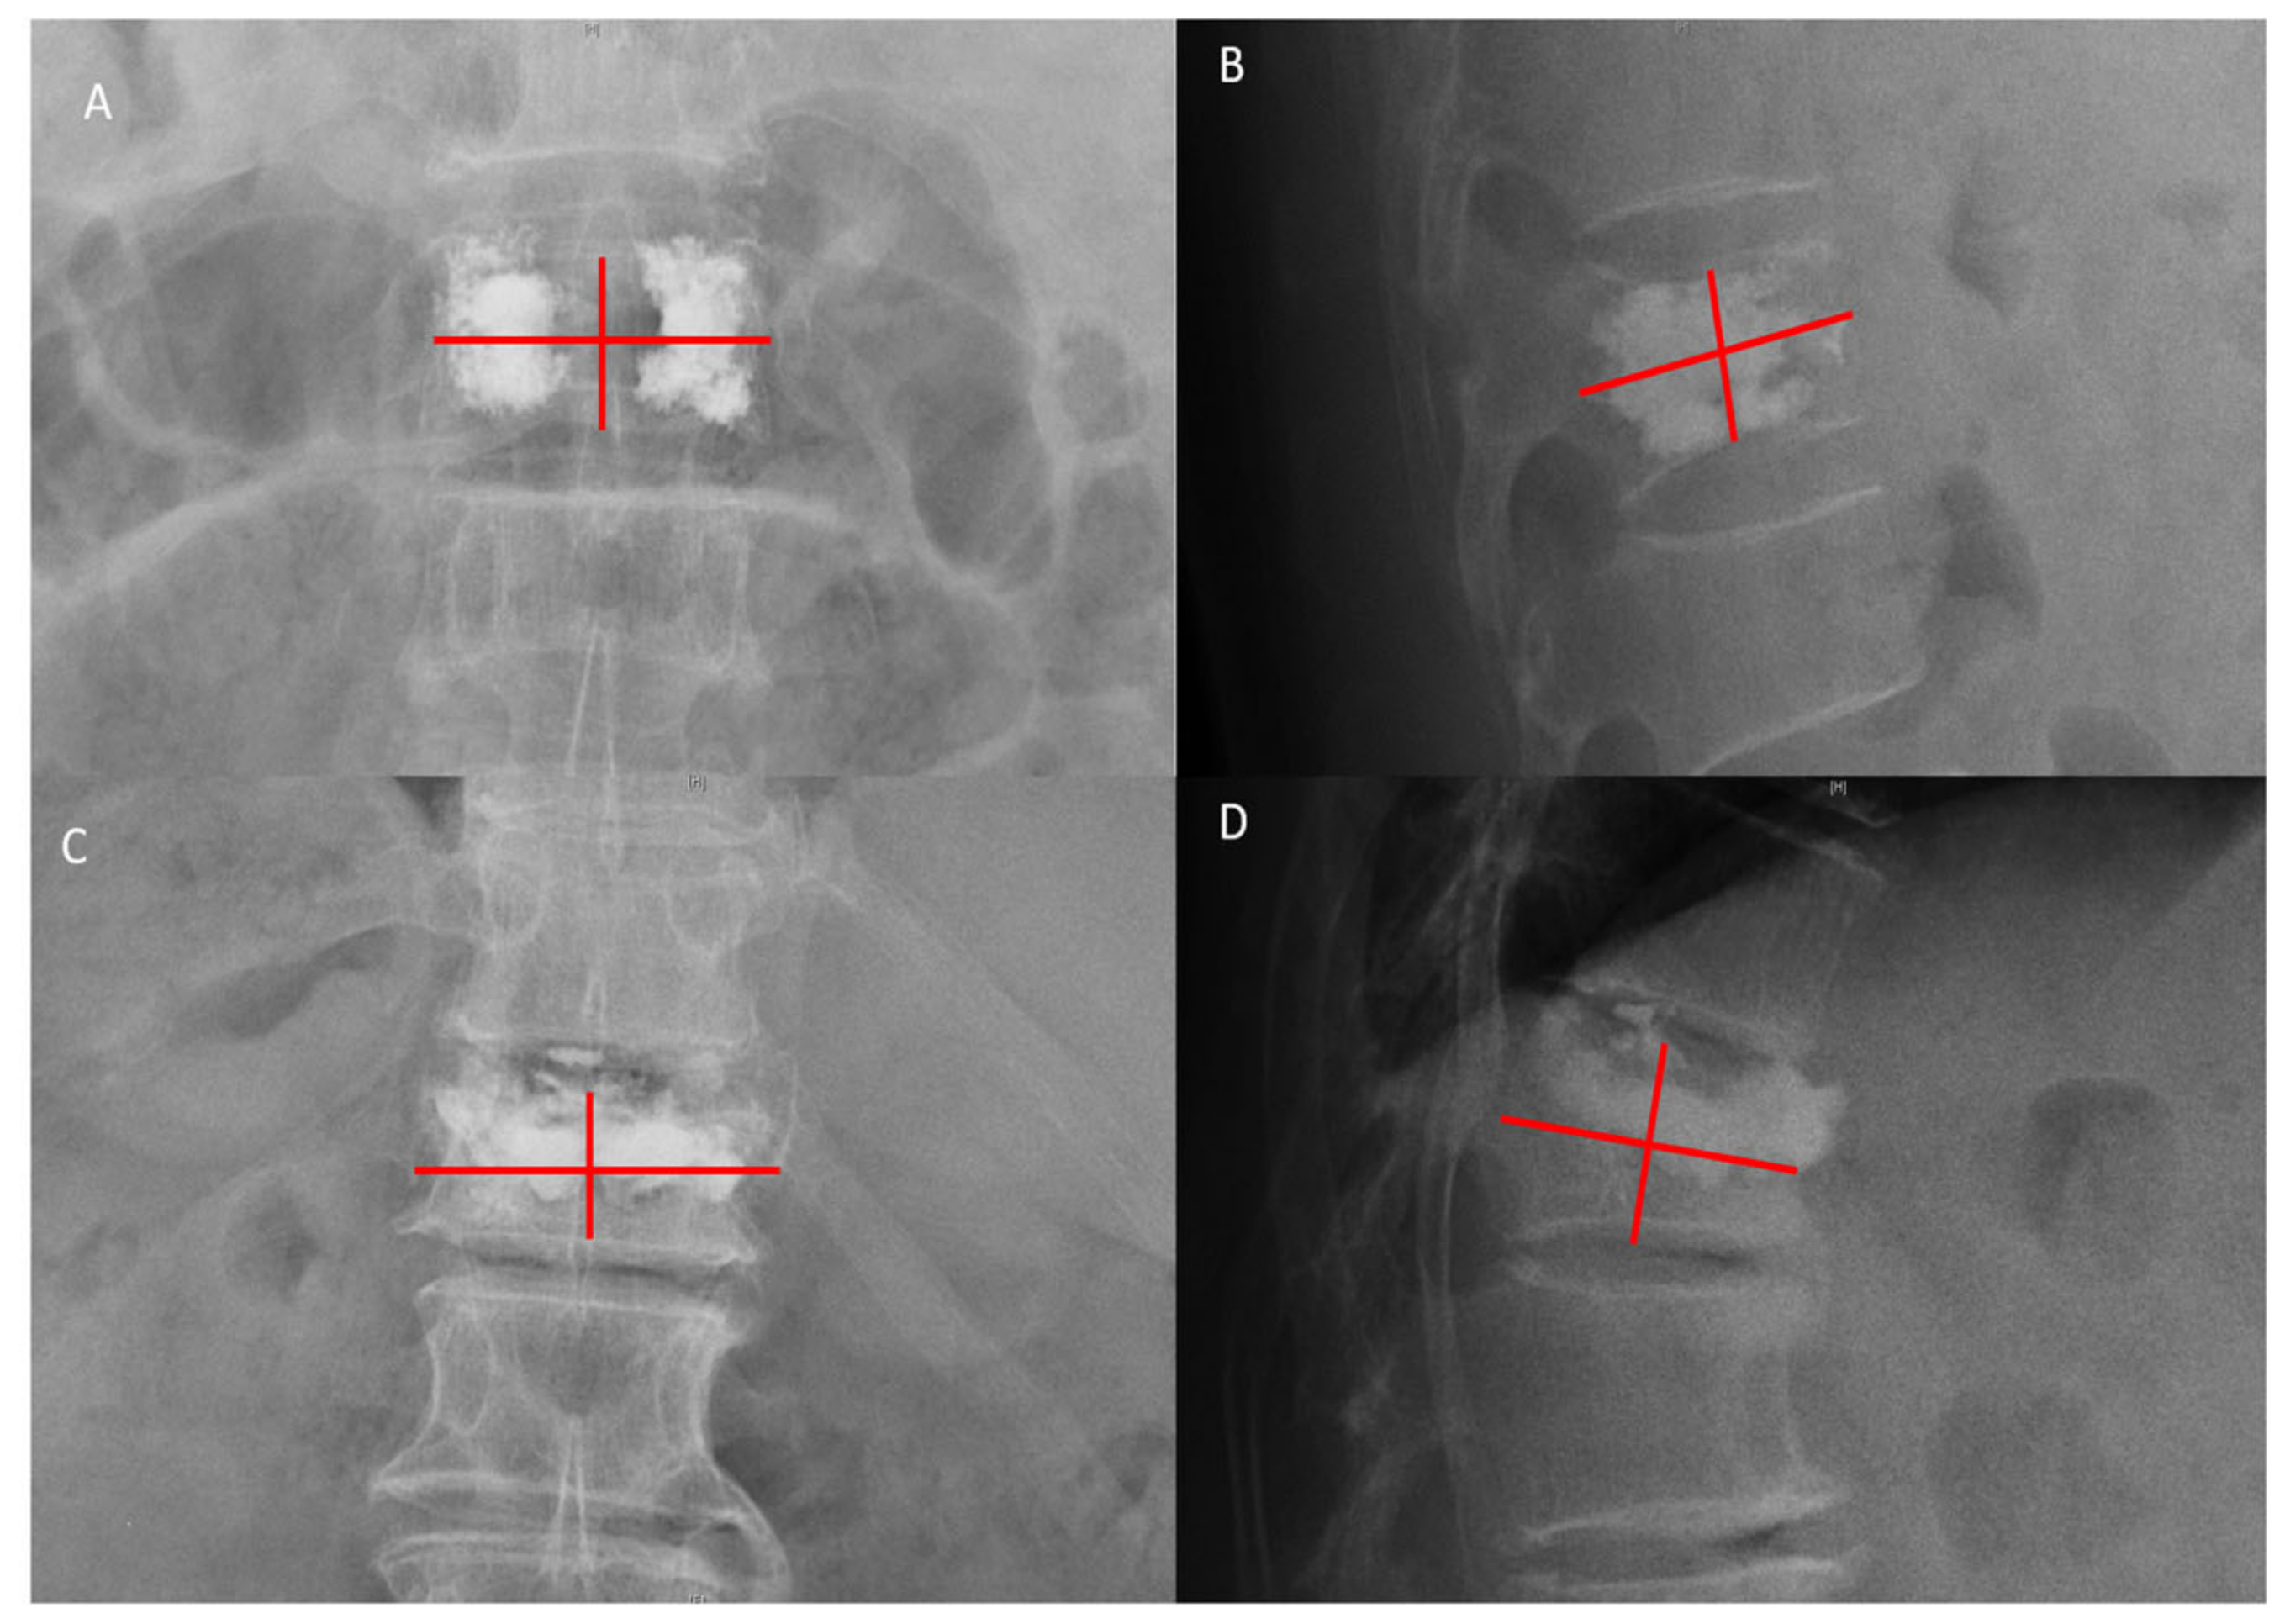

- Liu, J.; Tang, J.; Liu, H.; Gu, Z.; Zhang, Y.; Yu, S. A novel and convenient method to evaluate bone cement distribution following percutaneous vertebral augmentation. Sci. Rep. 2020, 10, 16320. [Google Scholar] [CrossRef]

- Lin, J.; Qian, L.; Jiang, C.; Chen, X.; Feng, F.; Lao, L. Bone cement distribution is a potential predictor to the reconstructive effects of unilateral percutaneous kyphoplasty in OVCFs: A retrospective study. J. Orthop. Surg. Res. 2018, 13, 140. [Google Scholar] [CrossRef]

- Lv, B.; Ji, P.; Fan, X.; Yuan, J.; Xu, T.; Yao, X.; Huang, A.; Zou, T. Clinical efficacy of different bone cement distribution patterns in percutaneous kyphoplasty: A retrospective study. Pain Physician 2020, 23, e409–e416. [Google Scholar]

| Bone cement distribution score | 0.814 | 0.790–0.835 | <0.001 |

| Bone cement distribution score | 7.73 ± 1.88 | 7.85 ± 1.76 | 8.08 ± 1.43 | <0.001 | 0.007 | 0.042 | 0.824 |